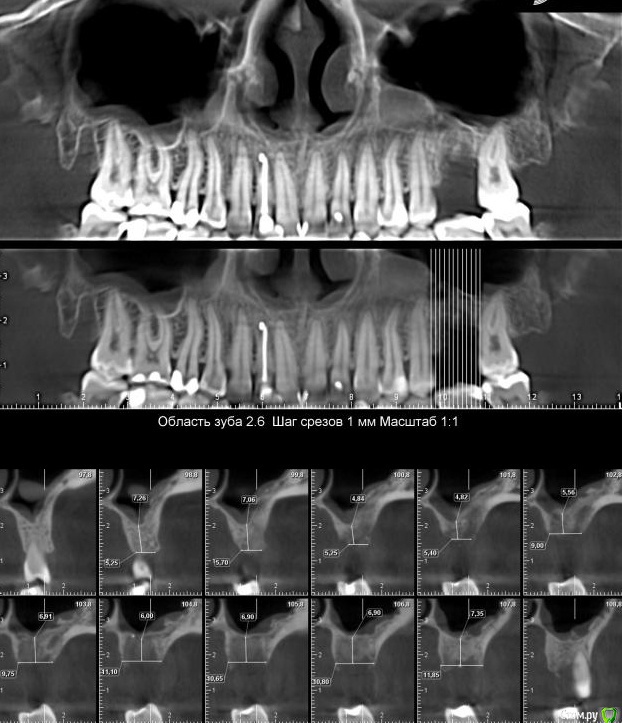

sole13 Опубликовано 10 августа, 2018 Автор Поделиться Опубликовано 10 августа, 2018 (изменено) уважаемые хирурги, прошу ваш совет 3 месяца назад было сделана имплантация 26 зуба, закрытый синус,сделано повторное свежее КТ через 3 месяца у меня ощущение постоянного комка слизи в носоглотке с момента операции (иногда отплевывается часть и это оч густое содержимое). пила 2 курса синупреда, 2 месяца на море, 2 курса ринофлоимуцила прокапала. если чуть заболеваю, то слева ощущение тяжести в крыле носа как при гайморите. хирург говорит, что перфорации гайморовой нет и в 50% случаях это нормальная реакция гайморовой - выделять слизь, что через месяца 3-4 у меня это пройдет. действительно гайморова пазуха не перфорирована и ощущение слизи -норма? еще меня смущает черная область вверху импланта справа на снимке и черное под имплантом и справа по вертикали - что это? Изменено 10 августа, 2018 пользователем sole13 Ссылка на комментарий

Neilrus Опубликовано 10 августа, 2018 Поделиться Опубликовано 10 августа, 2018 и я бы еще обратил внимание на 24 зуб, срезы бы посмотреть Ссылка на комментарий